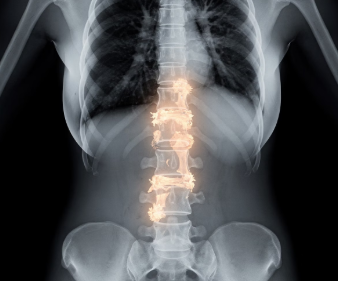

강직성 척추염은 척추와 천장관절(골반과 척추가 만나는 부위)에 만성 염증이 발생하는 자가면역성 질환입니다.

염증이 반복되면 뼈가 굳고 서로 붙으면서 척추 움직임이 제한될 수 있습니다.

14. 척추 변형

15. 강직(뼈가 붙는 현상)